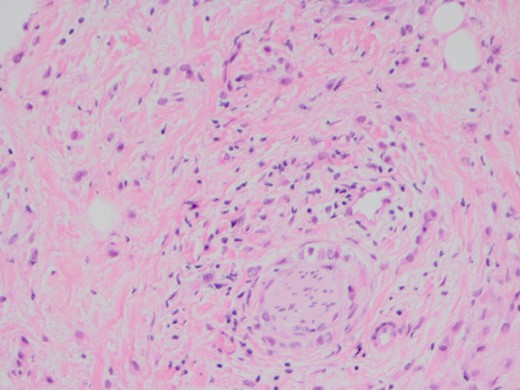

When she now presented with generalized abdominal pain, a CT scan of the abdomen was performed, revealing a lesion in the head of the pancreas measuring 7 × 4 cm2. This mass extended into the porta hepatis and towards the left lobe of the liver, opacification of the splenic vein and superior mesenteric veins was absent, and the confluence of the portal vein could also not be visualized (Fig. 1). Total bilirubin was 13 μmol/L (normal <20), raised ALT at 127 U/L (normal <34) and AST at 69 U/L (normal <31). ALP and GGT were also mildly raised at 135 U/L for ALP (normal 30–110) and 219 U/L for GGT (normal <38). Carcinoembryonic antigen and CA19.9, both markers of pancreatic cancer, were not raised. She was referred to a hepatobiliary surgeon for consideration of a pancreaticoduodenectomy, with the assumption of a primary pancreatic lesion. Due to suspected vascular involvement and potential peritoneal disease seen on the CT, she was regarded as an unsuitable candidate for a pancreaticoduodenectomy. To consider the use of palliative chemotherapy, a percutaneous biopsy for tissue diagnosis was performed. Histology demonstrated a poorly differentiated tumour, surrounded by benign pancreatic tissue with focal areas of perineural invasion by GATA3 positive epithelial cells. These cells also stained positive for ER, K19 and CEA, but negative for PR, B72.3, E-cadherin and HER2. The final diagnosis was poorly differentiated lobular breast carcinoma. Unfortunately, we were unable to compare the expression profiles between the pathology from the axillary dissection and the metastatic disease (Figs 2–4).

H and E stain demonstrating poorly differentiated carcinoma with perineural invasion.